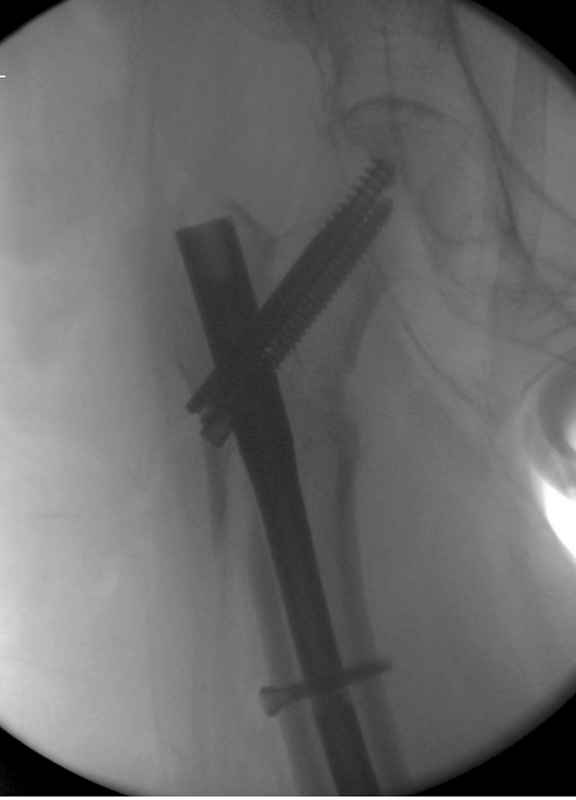

Здесь пара случаев фиксации похожих переломов:

первый высокоэнергетическая травма 36 лет

Djoldas Kuldjanov, M.D.

Department of Orthopedic Surgery

St. Louis University